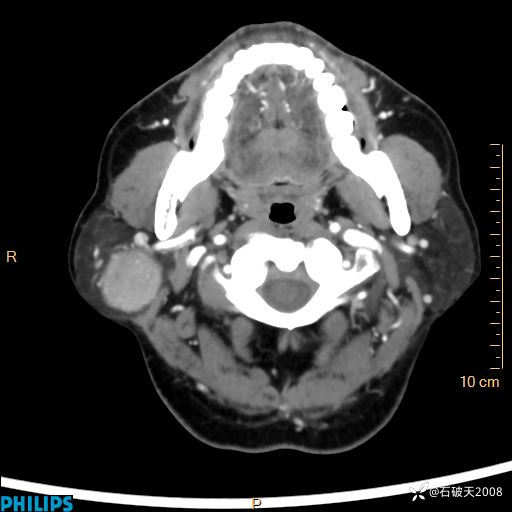

病例分享:颈部占位,一周后公布病理

男 57岁 主 诉:发现右侧颌下肿物1月余。

现病史:1月余前家属发现右侧颌下肿物。局部皮肤无红肿、热痛,无吞咽困难,无异物感,无恶心、呕吐,无头痛、头晕,无胸闷、胸痛,无发热、咳嗽、咳痰及呼吸困难。于我院行体表肿块彩超检查(2024.03.15我院)示:右侧耳下皮下软组织内低回声,未治疗。今为进一步治疗门诊以“腮腺肿瘤”为诊断收住我科,发病来患者神志清,精神可,饮食、睡眠及大小便正常,体重无明显下降。

动脉期